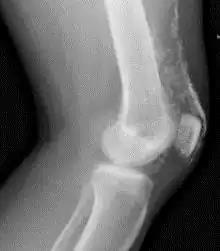

![]() Рентгенограмма коленного сустава пациента с дерматомиозитом. | |

Кальциноз мягких тканей (преимущественно мышц и подкожной жировой клетчатки) является особенностью ювенильного варианта заболевания, наблюдается в 5 раз чаще, чем при ДМ у взрослых [1], и особенно часто в дошкольном возрасте. Кальциноз может быть ограниченный или диффузный, симметричный или асимметричный, представляет собой отложение депозитов солей кальция (гидроксиапатитов) в коже, подкожной клетчатке, мышцах или межмышечных пространствах в виде единичных узелков, крупных опухолевидных образований, поверхностных бляшек. При поверхностном расположении кальцинатов возможна воспалительная реакция окружающих тканей, нагнаивание и отторжение их в виде крошковатых масс. Глубоко расположенные кальцинаты мышц, особенно единичные, можно выявить только при рентгенологическом исследовании.